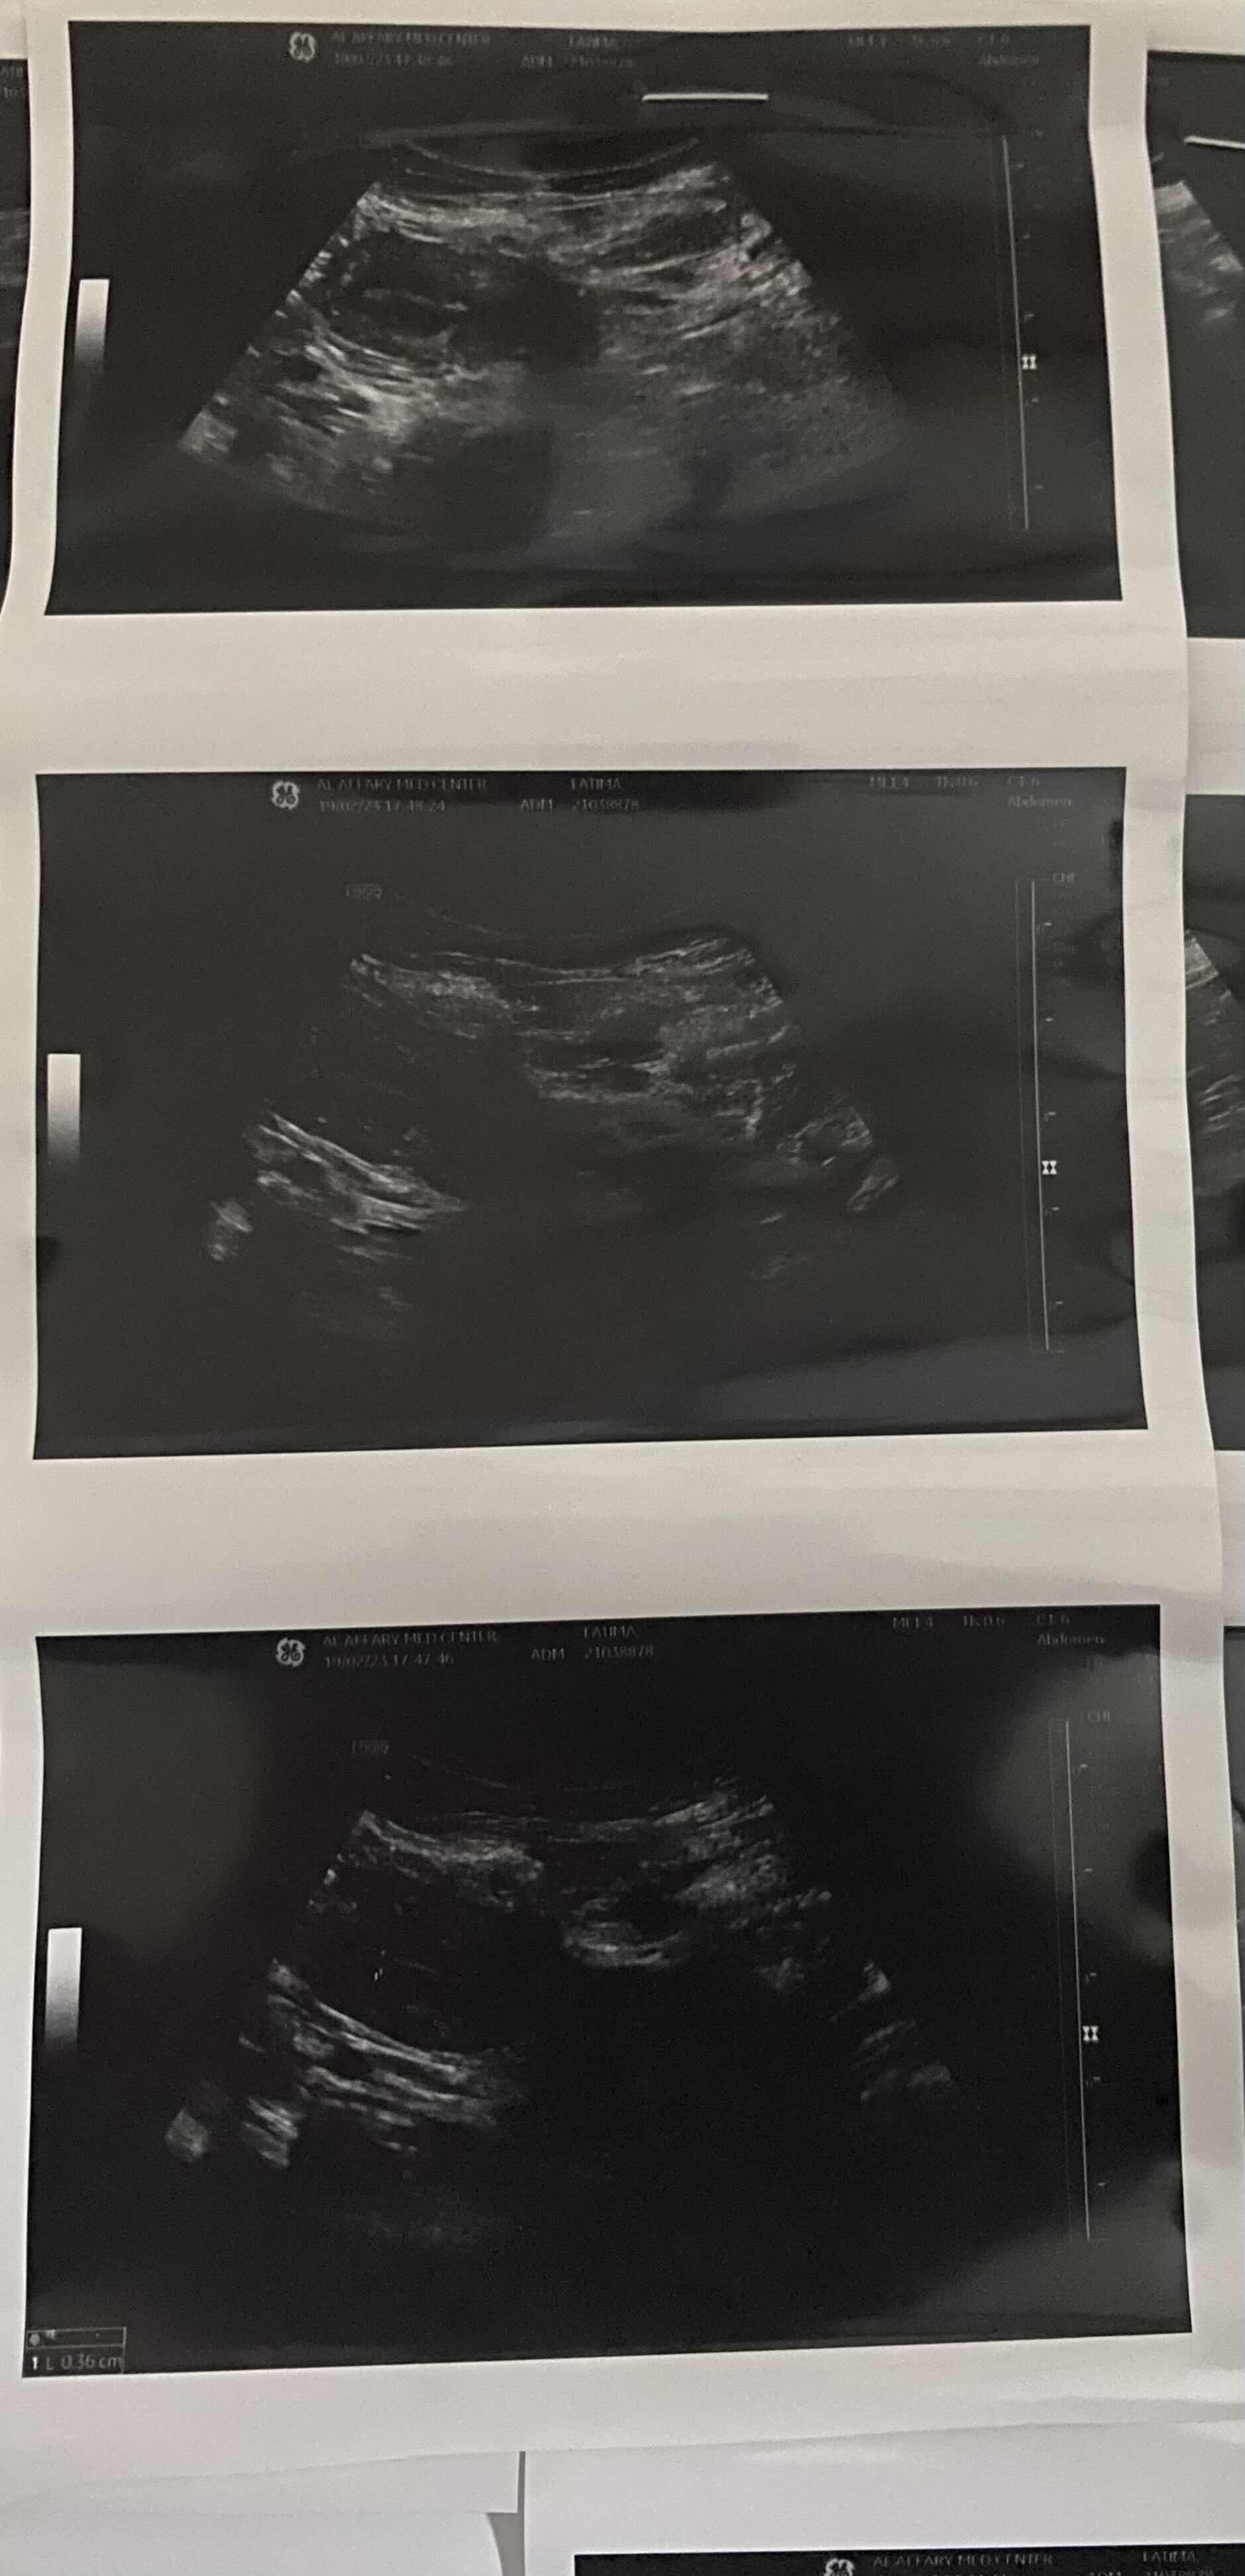

عودة الدورة بعد انقطاع الطمث انقطعت الدورة قبل ٨سنوات تقريبا